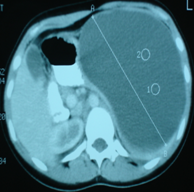

Abdominal CT scan. Hemorrhagic rupture of a simple hepatic cyst without active hemorrhage. The presence of free intraperitoneal fluid is noted (Courtesy Dr. V. Penopoulos)